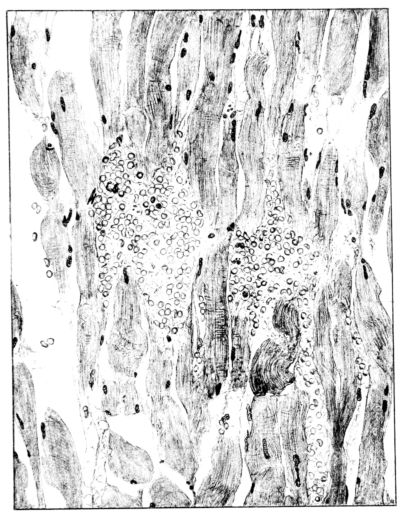

FIG. III. AUTOPSY NO. 90. DRAWING FROM A LESION OF THE TRACHEA (SOMEWHAT OLDER THAN THAT ILLUSTRATED IN FIGURE II). THE MUCOSA IS ENTIRELY LACKING. CONGESTION AND EDEMA ARE THE STRIKING FEATURES IN THE SUBMUCOSA. THE NECROTIZING PROCESS HAS EXTENDED INTO THE MUCUS GLANDS. THIS IS SHOWN IN THE LOWER PICTURE.

The changes are less marked, perhaps, in the trachea than in its finer ramifications. The mucosa is constantly more or less destroyed and large areas, usually focal, are entirely devoid of their epithelial covering. This is replaced by a sparse exudate, composed largely of red blood cells, mucus, a small amount of fibrin, and nuclear fragments (Fig. II). It may dip into the submucosa for a short distance, but usually these indentures are associated with the ducts of the mucous glands into which the inflammatory reaction extends. A more striking feature than the exudate, however, is the edema and the congestion of the submucosa. The loose areolar tissue of the submucosa is spread widely apart, and throughout it distended blood vessels are very conspicuous. Occasionally such a vessel is broken and actual hemorrhage appears in the submucosa. Occasionally, too, the inflammation extends down the duct to the mucous gland itself, and here, also, aplastic inflammatory reaction is evident, inasmuch as the acini now stain intensely red with the cells undifferentiated from each other and specked here and there by broken remains of the dead nuclei (Fig. III). After the disease has continued for a short period, even at the end of five or six days, some regeneration of the epithelial lining may be seen (3) (Fig. IV). But despite this, the acute picture persists, and there goes on, side by side, an attempted repair characterized by epithelial regeneration and the same evidence of acute change. Since the lesion is essentially a superficial one, scars or contractures of any extent are not encountered in the trachea, even in examples of the disease that have ended fatally only after many weeks.[4]